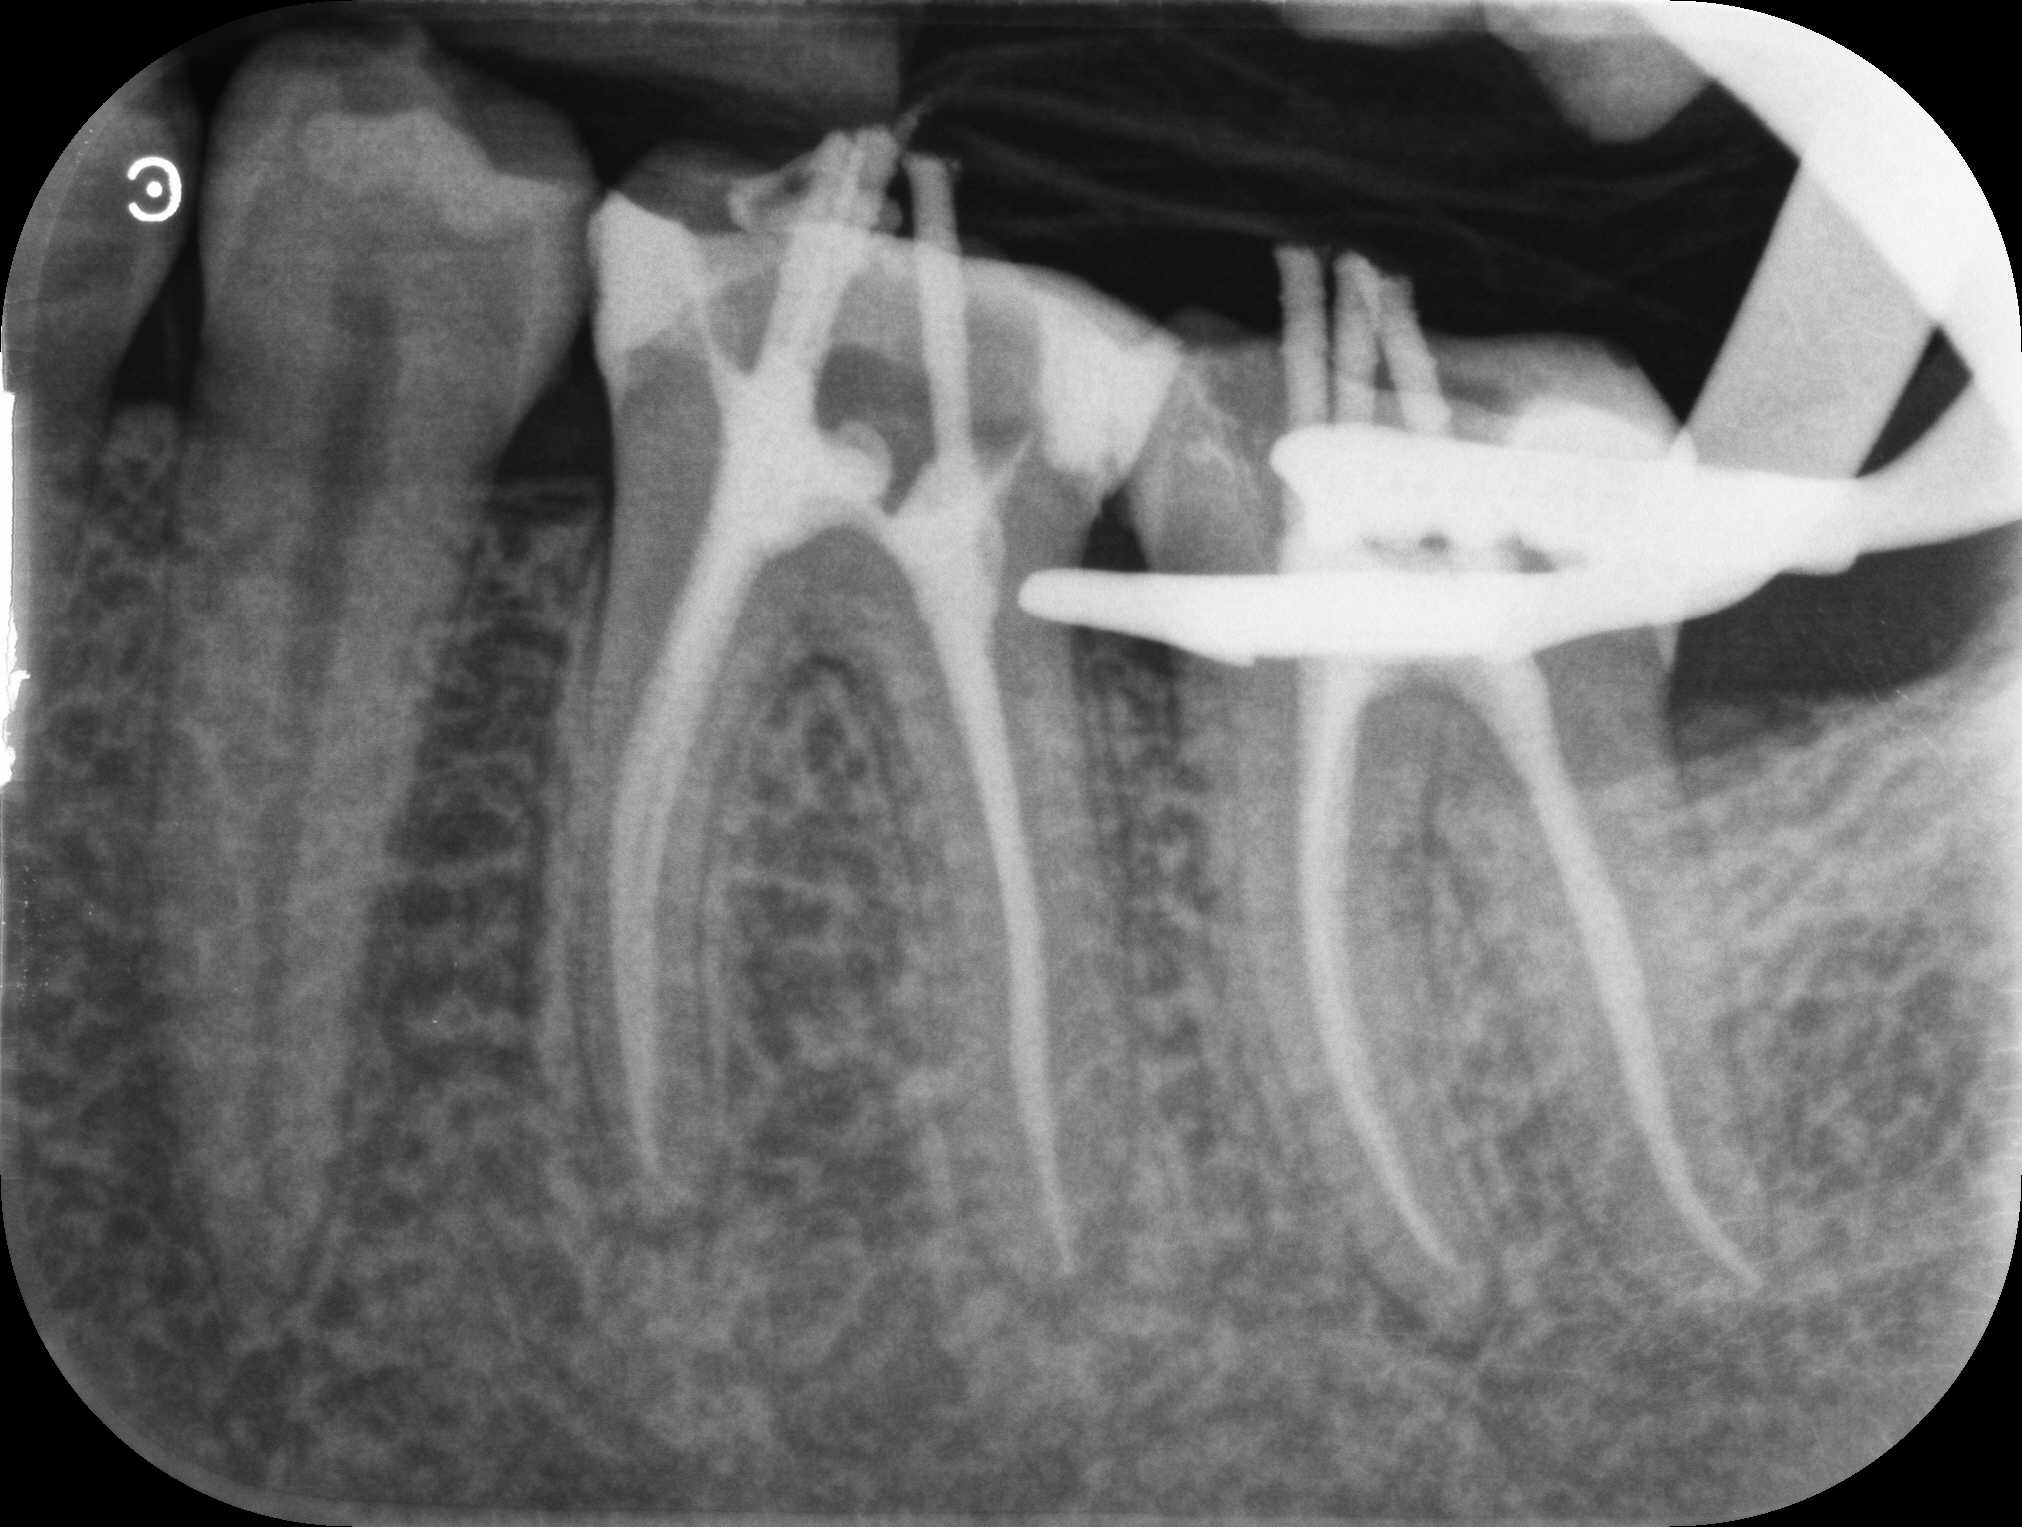

Ist der Defekt so tief, dass der Zahnnerv geschädigt wurde, so muss eine Wurzelbehandlung durchgeführt werden. Diese beinhaltet das saubere Entfernen

der Pulpa (Zahnnerv), die Desinfektion des Nervenkanals und eine bakteriendichte Füllung des Zahnes, um eine spätere Bakterienbesiedlung, welche zum Zahnverlust führen kann, zu verhindern.